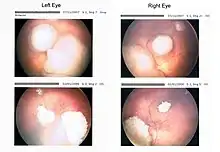

Intraocular malignancies are relatively more frequently treated than extraocular malignancies, likely due to a relatively earlier detection and subsequent treatment. Pediatricians may screen infants with annual vision tests, in which anomalies can be detected. During a red reflex test, light from an ophthalmoscope goes through transparent parts of the eye and reflects off the ocular fundus. If retinoblastoma is present, it may partially or fully impede light transversing this path. This may result in an abnormal red reflex or leucocoria, which can be a common indicator of retinoblastoma (when light is reflected by the tumor, the regular view of the red retina is blocked). The retinoblastoma may be visible as a whitish, translucent mass. If the tumor has not spread and is contained within the eye, chances of successful treatment are favorable. If initial signs are ignored or diagnosis is significantly delayed, outcomes and prognosis worsen. The effects of retinoblastoma may spread outside the eye, sometimes resulting in proptosis. Retinoblastoma that has spread may be significantly more difficult to treat. [7]

The most common and obvious sign of retinoblastoma is an abnormal appearance of the retina as viewed through the pupil, the medical term for which is leukocoria, also known as amaurotic cat's eye reflex.[4] Other signs and symptoms include deterioration of vision, a red and irritated eye with glaucoma, and faltering growth or delayed development. Some children with retinoblastoma can develop a squint,[8] commonly referred to as "cross-eyed" or "wall-eyed" (strabismus). Retinoblastoma presents with advanced disease in developing countries and eye enlargement is a common finding.[9]

Depending on the position of the tumors, they may be visible during a simple eye examination using an ophthalmoscope to look through the pupil. A positive diagnosis is usually made only with an examination under anesthetic (EUA). A white eye reflection is not always a positive indication of retinoblastoma and can be caused by light being reflected badly[10] or by other conditions such as Coats' disease.[11]

The presence of the photographic fault red eye in only one eye and not in the other may be a sign of retinoblastoma. A clearer sign is "white eye" or "cat's eye" (leukocoria).[12]